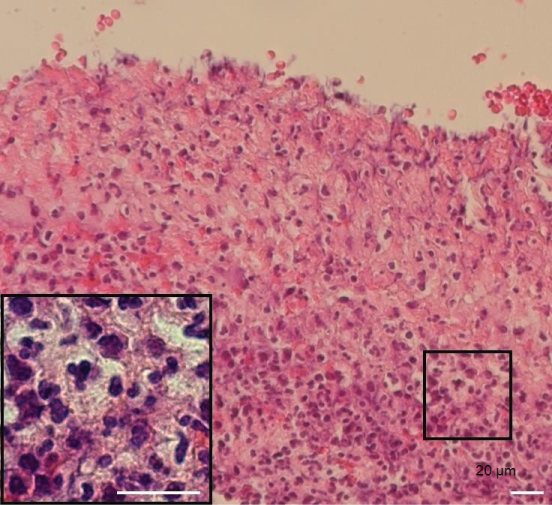

Histologically, there was no epithelial layer or ulcerative tissues with subepithelial inflammatory infiltrates containing plasma cells (Figure 2). Results of blood examination were within normal range: WBC, 6,000/µL; RBC, 511 × 104/µL; hemoglobin, 14.2 g/dL; platelet, 25.1 × 104/µL; prothrombin time-international normalized ratio (PT-INR), 0.99; activated partial thromboplastin time (APTT), 28.8 sec; C-reactive protein (CRP), 0.06 mg/dL; desmoglein 1, < 5; desmoglein 3, < 5; BP-180, 5.7; rheumatoid factor, 5 IU/mL; antinuclear antibody, < 40. Commonly existing oral bacteria, Streptococcus and Neisseria, were isolated from the surface of the ulcers.

Figure 2: Histology showing subepithelial connective tissues along with chronic inflammatory cells (H-E stain; bar, 20 µm). The square shows the area containing plasma cells. View Figure 2